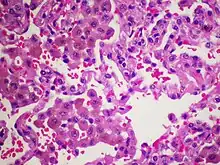

Desquamative interstitial pneumonia (DIP) is a form of idiopathic interstitial pneumonia featuring elevated numbers of macrophages within the alveoli (air sacs) of the lung. The alveolar macrophages have a characteristic light brown pigmentation and accumulate in the alveolar lumen and septa regions of the lower lobes of the lungs.[1] The typical effects of the macrophage accumulation are inflammation and later fibrosis (thickening and stiffness) of the lung tissue.[2]